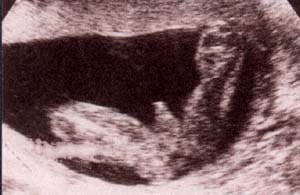

fig. 50.– (a). pene y bolsa escrotal. 17 semanas. fig. 50. – (b). 21 semanas. los testículos aún no descendidos.